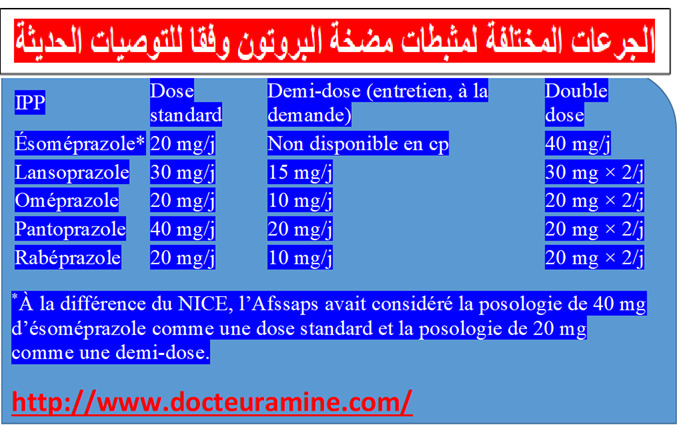

تحتل أدوية م م ب المحل الرئيسي في أخذ موقف علاج حالة الارتجاع المعدي المريئي. يبات ا م م أقل حموضة وبالتالي أقل تسمما للغشاء المخاطي المريني (13) الأمر الذي يؤول الى سرعة التئام الآفات أو جروح الالتهابات المريئية (14). بجانب تحقيق وتراجع الأعراض الناجمة عن الارتجاع المعدي المريئي يتم اللجوء الى تناول م م ب . بجانب تحقيق وتراجع اعراض الناجمة عن الارتجاعي المعدي المريئي. يتم اللجوء لتناول م م ب قصد التئام التهاب المريء الناجم عن حالة الترجيع المعدي المريئي للوقاية ضد الانتكاسات التي تبرز بعد التئام الجراح بجانب علاج حالة الجزر المعدي المريئي الذي تخلفه عقاقير ا م م البروتون التميز بالأعراض السريرية و وجود الدم في البراز. تختلف الجرعات الموصي بها حسب وجود أو عدم التهاب المريء. يلخص جدول رقم 1

ترخيصات تسويق مثبطات مضخة البروتون.

توصف م م ب جرعة كاملة (17). بينما نكتفي بأربعة أسابيع لعلاج التهاب المريء الغير شديد ومن أجل الوقاية بواسطة مم ب جرعة كاملة أو نصف الجرعة تصديا للانتكاسات